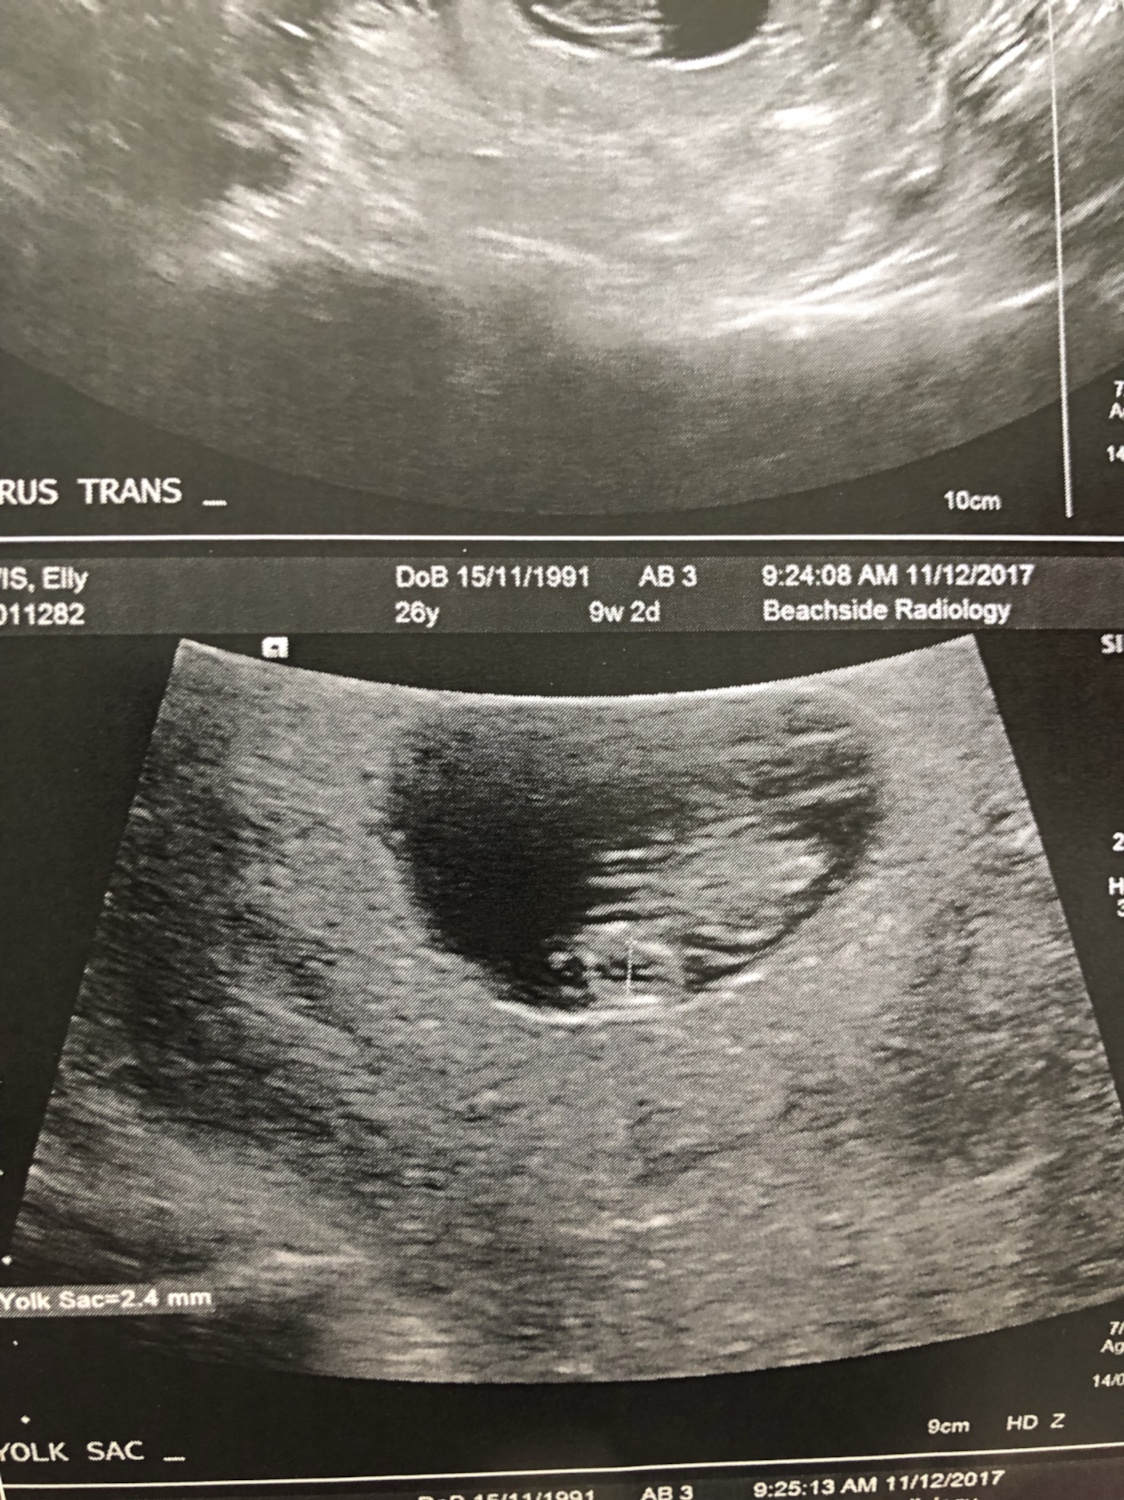

So I’m 8 weeks and 1 day today and I had my scan. It was abdominal not vaginal so I know that sometimes it can be flipped. I completely forgot to ask what side the placenta was on so fingers crossed someone can give me an idea on what I’m looking at! Thanks

Attachment 38386Attachment 38387Attachment 38388